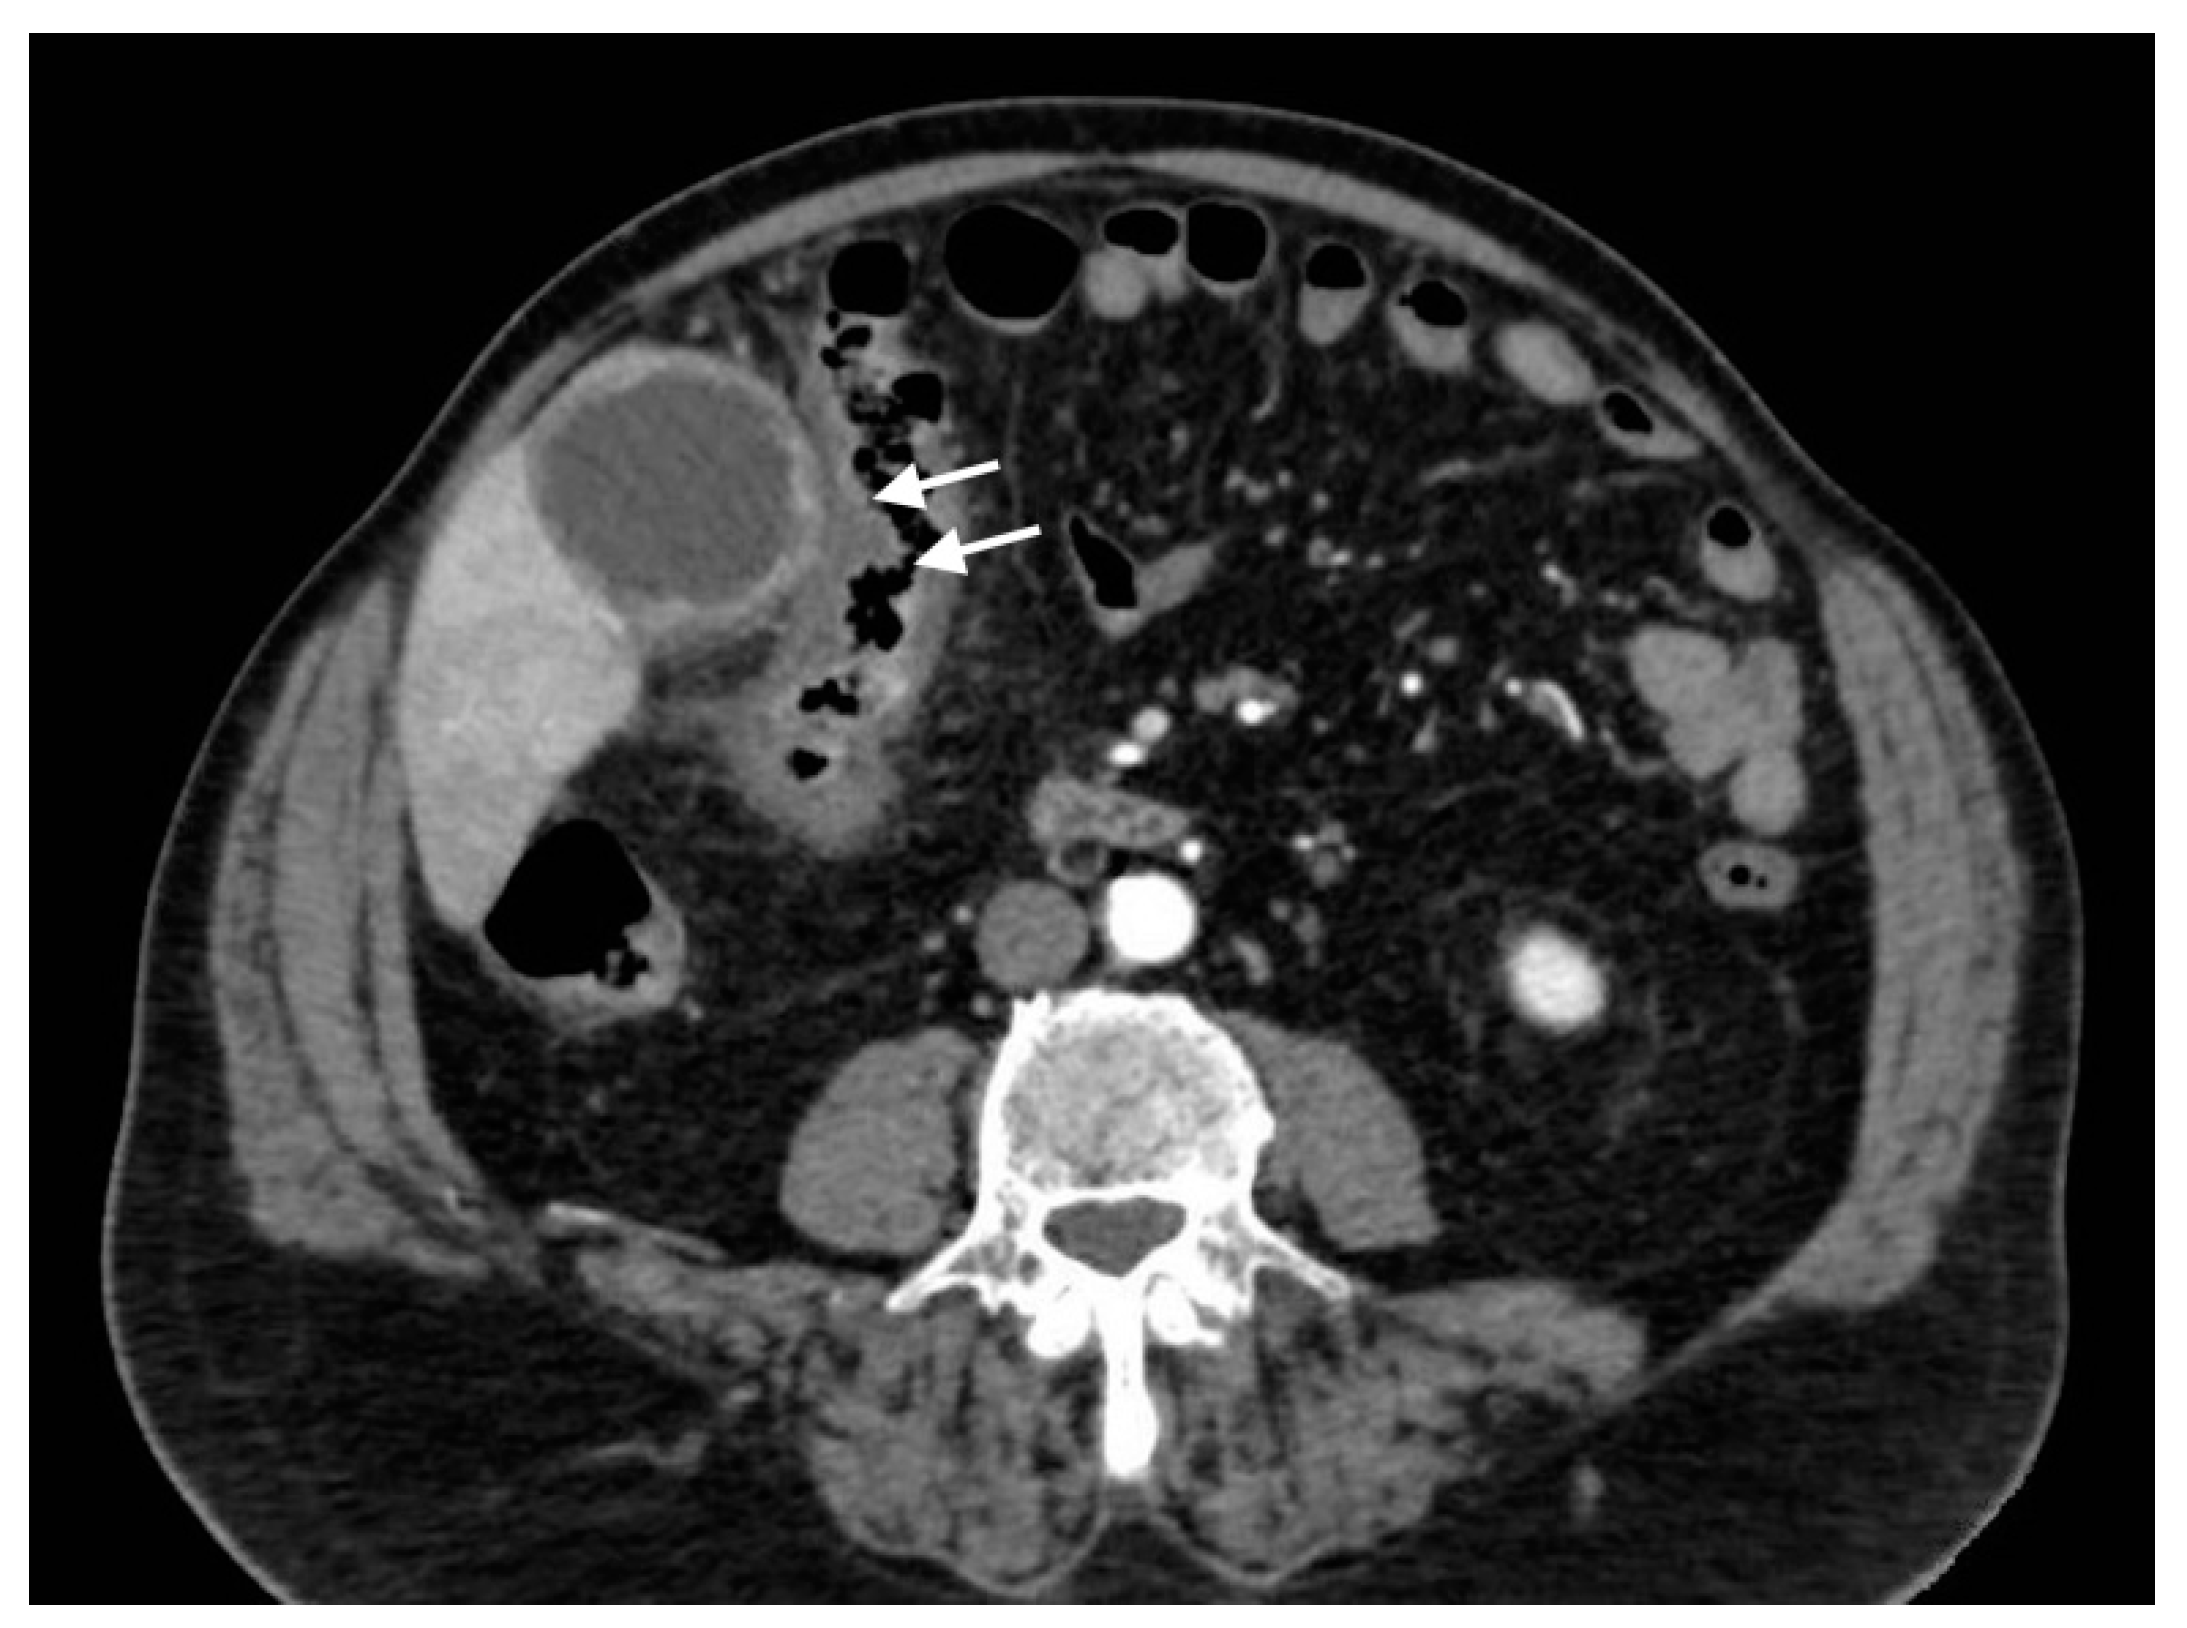

Figure 13.

Gangrenous cholecystitis with colitis: axial scan shows the signs of pericholecystic inflammation that extend to the right colic flexure with diffuse colic wall thickening (white arrows).